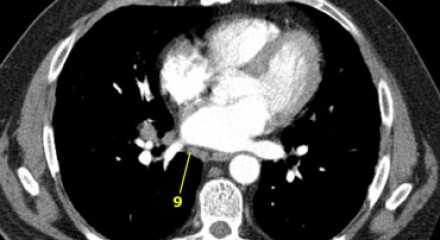

9. лимфатические узлы легочной связки

Данные лимфатические узлы лежат в пределах легочной связки, в том числе и по ходу нижней легочной вены. Легочная связка представлена дупликатурой медиастинальной плевры охватывающей корень легкого.